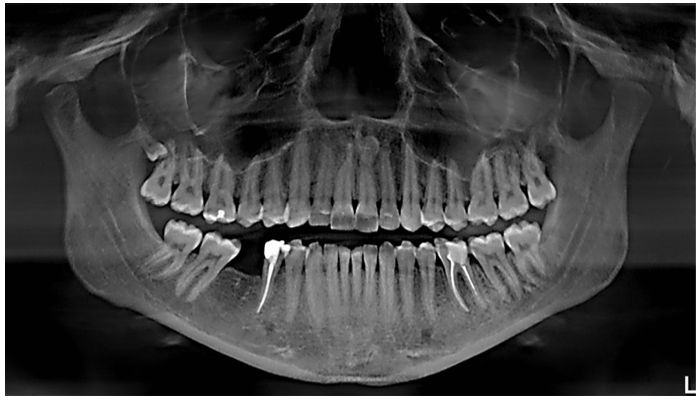

Панорамный

Один из самых популярных методов обследования перед лечением. Такой снимок зубов для брекетов называется панорамный, поскольку позволяет судить о том, в каком состоянии все зубы пациента.

- Панорамное изображение дает возможность проанализировать последствия лечения зубов, состояние их корневой части, тканей пародонта. Можно увидеть, насколько качественны протезы или коронки, установленные в полости рта пациента. Ортодонты на таких снимках определяют наличие зубных элементов сверх комплекта, в зачаточном состоянии, а также состояние костной ткани.